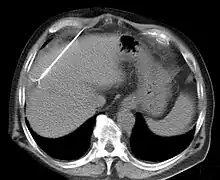

Documented benefits have led to RFA becoming widely used during the 21st century.[4][5][6] RFA procedures are performed under image guidance (such as X-ray screening, CT scan or ultrasound) by an interventional pain specialist (such as an anesthesiologist), interventional radiologist, otolaryngologists, a gastrointestinal or surgical endoscopist, or a cardiac electrophysiologist, a subspecialty of cardiologists.

RFA may be performed to treat tumors in the lung,[7][8][9] liver,[10] kidney, and bone, as well as other body organs less commonly. Once the diagnosis of tumor is confirmed, a needle-like RFA probe is placed inside the tumor. The radiofrequency waves passing through the probe increase the temperature within tumor tissue, which results in destruction of the tumor. RFA can be used with small tumors, whether these arose within the organ (primary tumors) or spread to the organ (metastases). The suitability of RFA for a particular tumor depends on multiple factors.